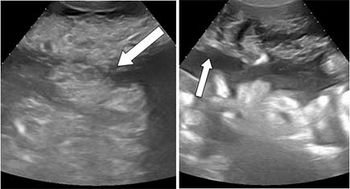

Case History: 75-year-old patient presented with complaints of six months of abdominal distension, generalized abdominal pain and breathlessness when lying down.